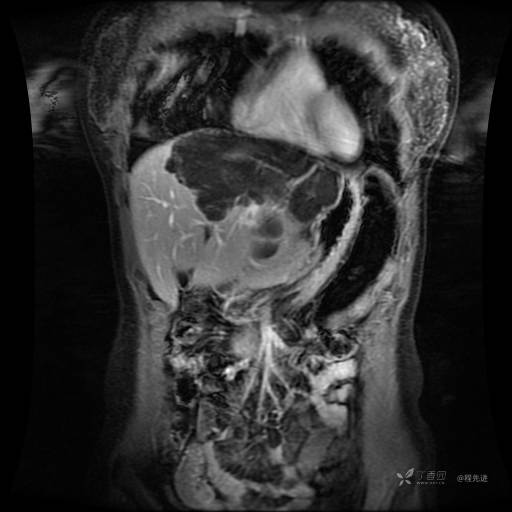

MR平扫+增强

每个序列一张图像(图像太多了,恕不一一发上来)